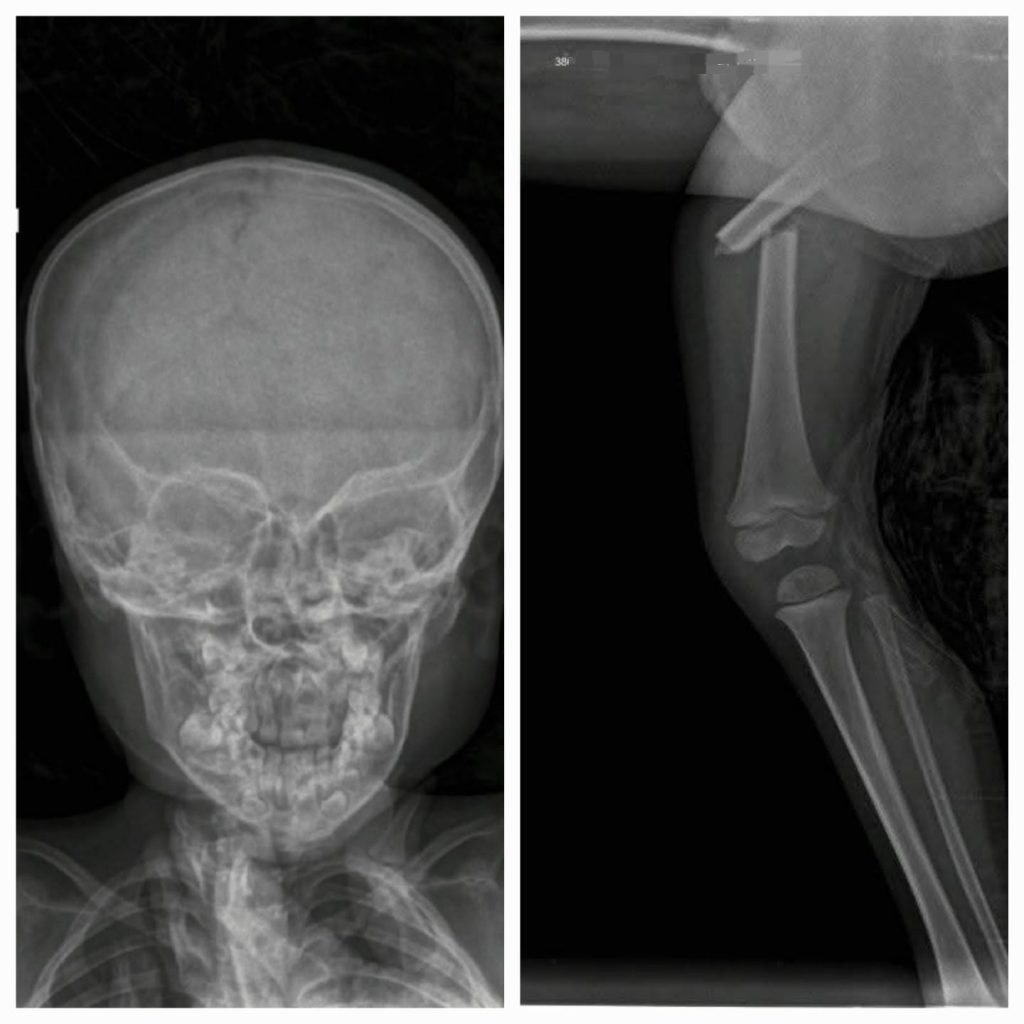

Un grave accidente sacudió a la ciudad de Frías, cuando un niño de apenas 3 años fue atropellado en inmediaciones de la sede policial.

Según el relato de familiares, el pequeño, sobrino de Mari Lobo, fue embestido por un automóvil conducido por una mujer. Tras el impacto, el menor fue trasladado de inmediato al hospital local, donde recibió la primera asistencia médica.

Mientras tanto, el pequeño permanece internado bajo observación médica, y su estado es seguido de cerca por los profesionales de la salud.